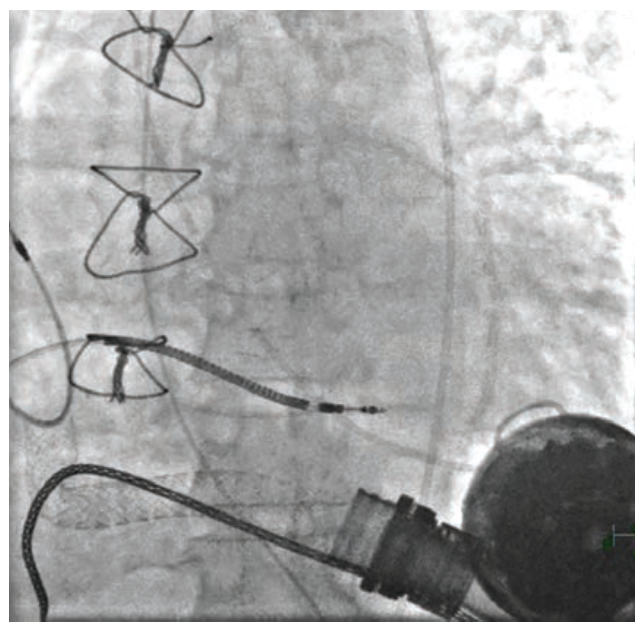

Initially, we attempted to snare the stent from both sides via two vascular accesses. To snare the upper portion of the stent, a 20 mm Amplatz Goose Neck snare (Medtronic) was introduced through a 23 cm 8 French (F) sheath in the right internal jugular vein. Simultaneously, a 30 mm Amplatz Goose Neck snare was introduced through a 30 cm 14F sheath in the right femoral vein to snare the bottom part of the stent. This method of stent retrieval was not successful; therefore, we had to rethink our strategy.

We upsized the 14F sheath to 24F and placed a second 20F sheath within it. We put a third 16F sheath inside these two previous 24F and 20F sheaths. Dr. Nelson Bernardo, an interventional cardiologist at Medstar Washington Hospital Center, practices this technique, known as mother-child-grandchild. The two snares described previously were used to capture both sides of the stent with the top snare pulling from the top and the bottom snare pulling from below, preventing the stent from embolizing into the right ventricle and slowly bringing it down into the inferior vena cava. The traction of the stent’s edge elongated it and made it smaller, which allowed us to capture its middle portion with a third 35 mm Amplatz Goose Neck snare. The stent was then pulled as a unit into the 16F sheath. Then the stent was pulled together with the 16F and 20F sheaths, taking them out of the 24F sheath as a single unit. A repeat fluoroscopy was performed to ensure that no residual pieces were left behind, and an angiogram was performed to confirm that there was no evidence of dissection. Upon examination, the stent was found to be intact and to have been endothelialized much earlier than expected. In the common femoral vein, hemostasis was achieved using a Perclose (Abbott). While in the internal jugular vein, hemostasis was achieved by manual compression.